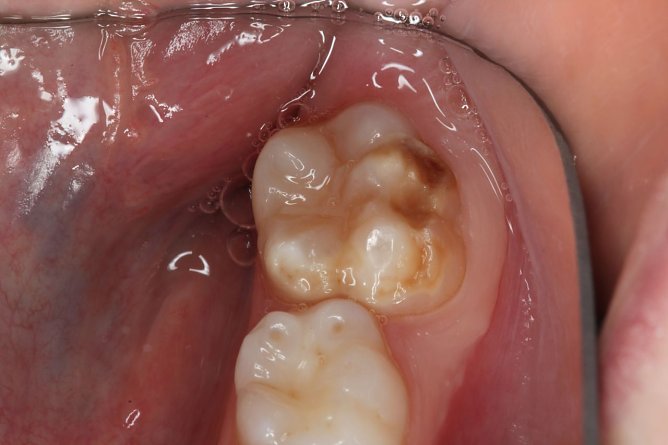

Bei Kreidezähnen handelt es sich eine Schmelzbildungsstörung, die meist an den ersten bleibenden Backenzähnen auftritt, häufig auch an den bleibenden Frontzähnen. Milchzähne können ebenfalls betroffen sein. Es bilden sich weiße bis gelblichbraune Flecken – je größer und dunkler die verfärbten Stellen sind, desto stärker ist die Störung. Bei schweren Fällen ist der Zahnschmelz stark geschwächt und bricht ein, daher auch der Begriff Kreidezähne. Bei den schwächeren Ausprägungen sind die Zähne nur verfärbt. In den meisten erkannten Fällen von Kreidezähnen haben die jungen Patienten starke Schmerzen, insbesondere beim Zähneputzen und Essen. Daraus können sich Ängste entwickeln. Zudem können unbehandelte Kreidezähne langfristig zu schlechter Mundhygiene und Karies führen, verdeutlicht Birgit Dziuk. Eltern müssten sich aber keine Vorwürfe machen. Bei Kreidezähnen handle es sich um Schädigungen der Zähne, die nicht durch mangelhafte Mundhygiene entstehen. Wichtig sei, dass die Störung frühzeitig erkannt und behandelt wird.